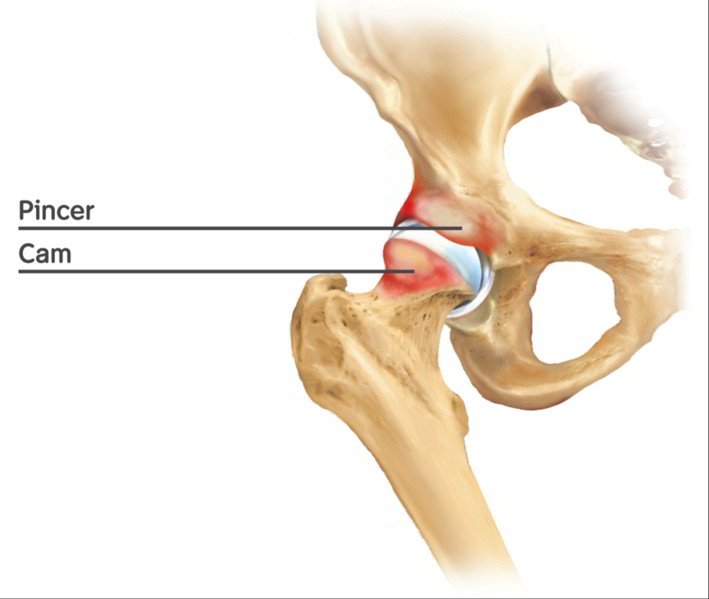

Links: gesundes Hüftgelenk. Mitte: Cam-Impingement mit einer Deformität des Oberschenkelkopfes. Rechts: Pincer-Impingement mit einer Deformität der Hüftgelenkspfanne. © Gelenk-Klinik

Hüftgelenk mit kombiniertem Cam-Impingement am Oberschenkelkopf und Pincer-Impingement an der Hüftgelenkspfanne. © Istockphotos